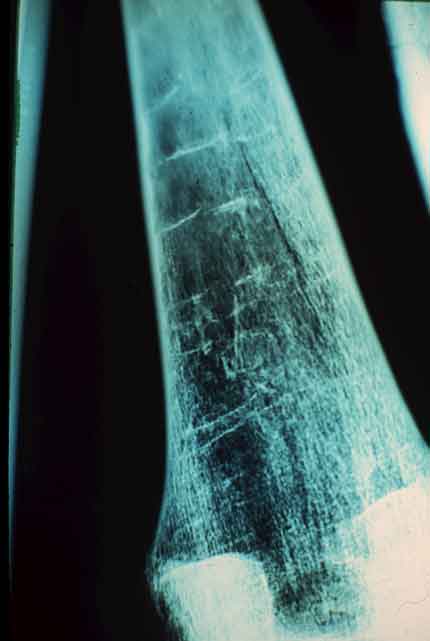

Paradas temporárias de crescimento do organismo, e sua recuperação, podem ser identificadas pela presença de linhas de Harris, visíveis nas radiografias dos ossos longos.